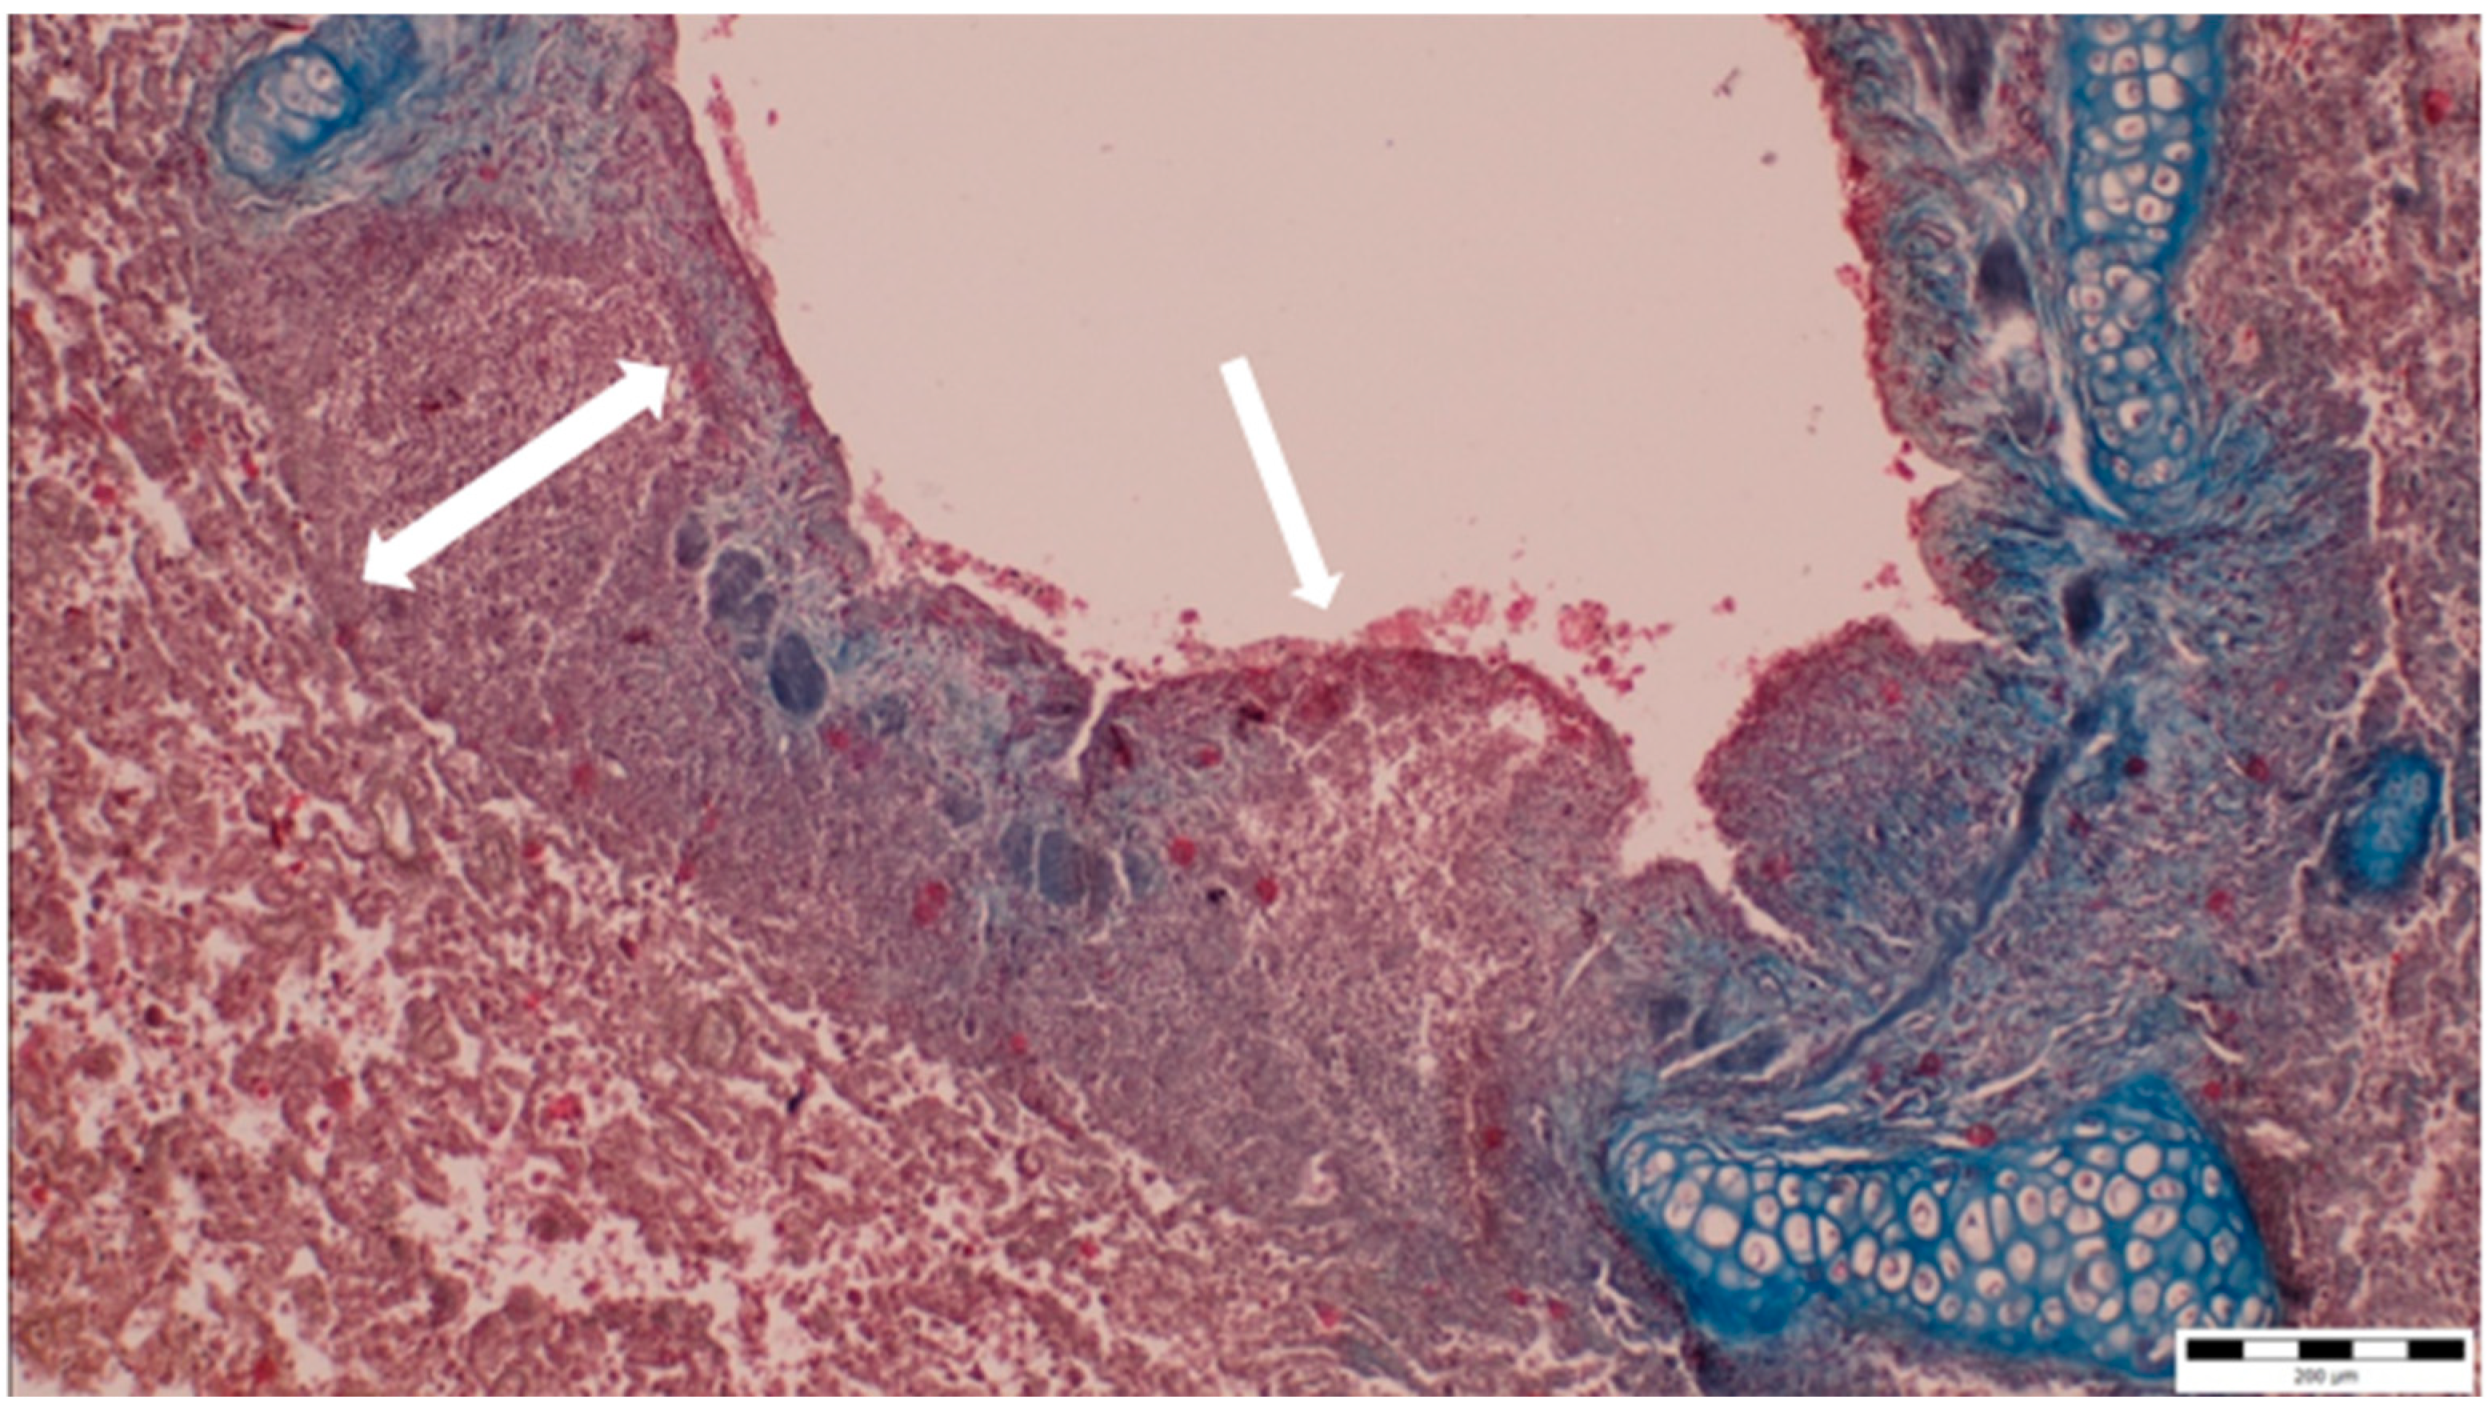

A histopathological examination of the bronchi revealed an interstitial lymphohistiocytic infiltrate characterized by a dense accumulation of lymphocytes and histiocytes within the bronchial walls. There was marked thickening and partial desquamation of the bronchial epithelium (Figure 2). Multifocal liquefactive necrosis, intermixed with clusters of lymphocytes, was observed (Figure 3). Additionally, purulent bronchial exudate, containing numerous neutrophils and macrophages, was present, contributing to the thickening and partial desquamation of the bronchial wall (Figure 4). An area of liquefactive necrosis was demarcated by a lymphohistiocytic infiltrate, predominantly composed of lymphocytes (Figure 5).

Figure 2.

Interstitial lymphohistiocytic infiltrate, along with thickening (two-way arrow) and partial shedding of the bronchial epithelium (white arrow) (obj. ×10).